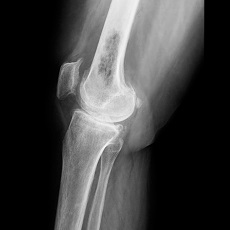

- Osteosarcoma - occurs most often between ages 10 and 19. It is more common in the knee and upper arm.

The most common symptom of bone cancer is pain. Other symptoms vary, depending on the location and size of the cancer. Surgery is often the main treatment for bone cancer. Other treatments may include amputation, chemotherapy, and radiation therapy. Because bone cancer can come back after treatment, regular follow-up visits are important.